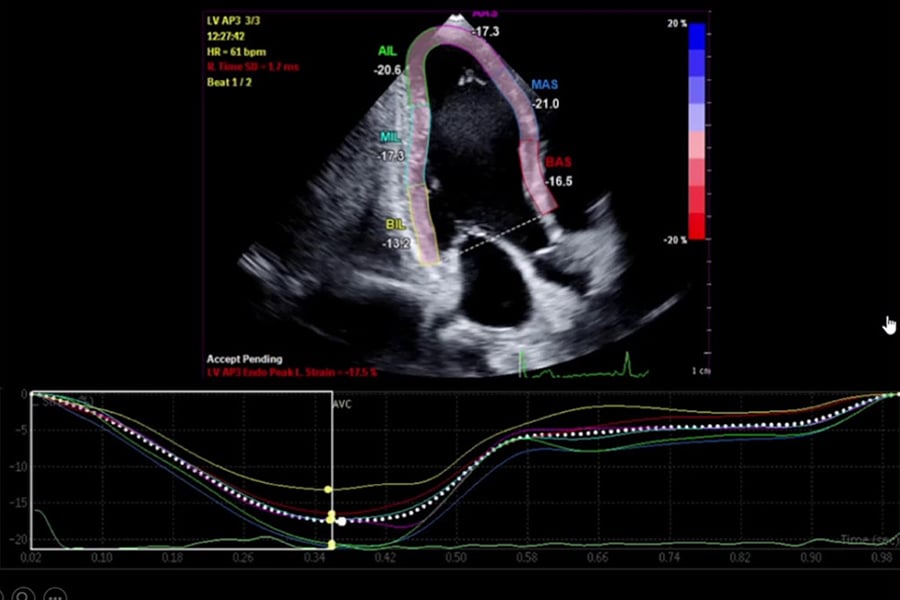

امکانات ویژه این کلینیک در برگیرنده انواع اکوکاردیوگرافیهای فوقتخصصی است. این موارد شامل اکوکاردیوگرافی پیشرفته، استرس اکوکاردیوگرافی، اکوکاردیوگرافی مری و کنتراست اکو است.

اکوکاردیوگرافی پیشرفته، شامل استفاده از دستگاهها و تکنولوژی جدید و مدرن اکوکاردیوگرافی برای بررسی بیماریهای قلبی است که توسط فلوشیپهای فوقتخصصی اکوکاردیوگرافی انجام میشود. در بعضی موارد، بیمارانی که اختلال جدی در عملکرد عضله قلب یا دریچههای قلب، و یا بیماری مادرزادی قلبی دارند و اکوکاردیوگرافی اولیه آنها توسط سایر همکاران متخصص قلب انجام شده است، جهت بررسی دقیقتر و تصمیمگیری نهایی، تحت اکوکاردیوگرافی پیشرفته قرار میگیرند.